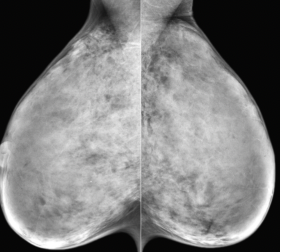

dense breasts

fatty breasts